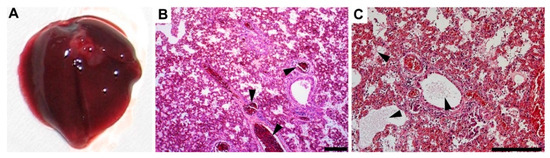

3.4. Gross Pathology Appearance and Histopathological Changes